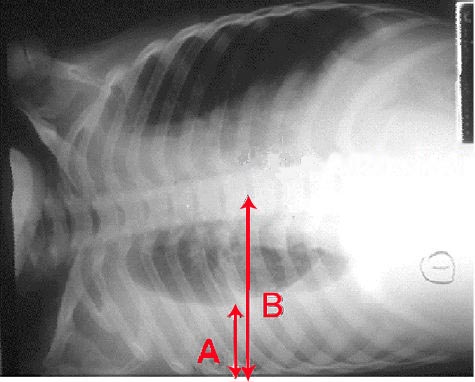

폐렴의 X선 사진 소견은 섬엽 폐렴, 세기관지 폐렴, 소엽 폐렴, 간질성 폐렴으로 분류할 수 있다.[66] 세균성, 급성 폐렴은 고전적으로 폐 분절엽 하나의 폐 실질 침윤을 보이는데, 이를 섬엽 폐렴이라고 한다.[72] 그러나 소견은 다양할 수 있으며, 다른 유형의 폐렴에서는 다른 양상이 흔하다.[72] 흡인성 폐렴은 주로 폐 아래쪽과 오른쪽에 양측성 음영으로 나타날 수 있다.[72] 바이러스성 폐렴의 X선 사진은 정상, 과팽창, 양측성 반점, 또는 섬엽 폐렴과 유사한 폐 실질 침윤으로 나타날 수 있다.[72] 특히 탈수가 있는 경우 질병 초기에는 방사선학적 소견이 없거나, 비만 또는 폐 질환 병력이 있는 사람은 해석하기 어려울 수 있다.[140] 흉막 삼출과 같은 합병증도 흉부 방사선 사진에서 발견될 수 있다. 측면 흉부 방사선 사진은 폐 실질 침윤과 흉막 삼출 진단 정확도를 높일 수 있다.[78]